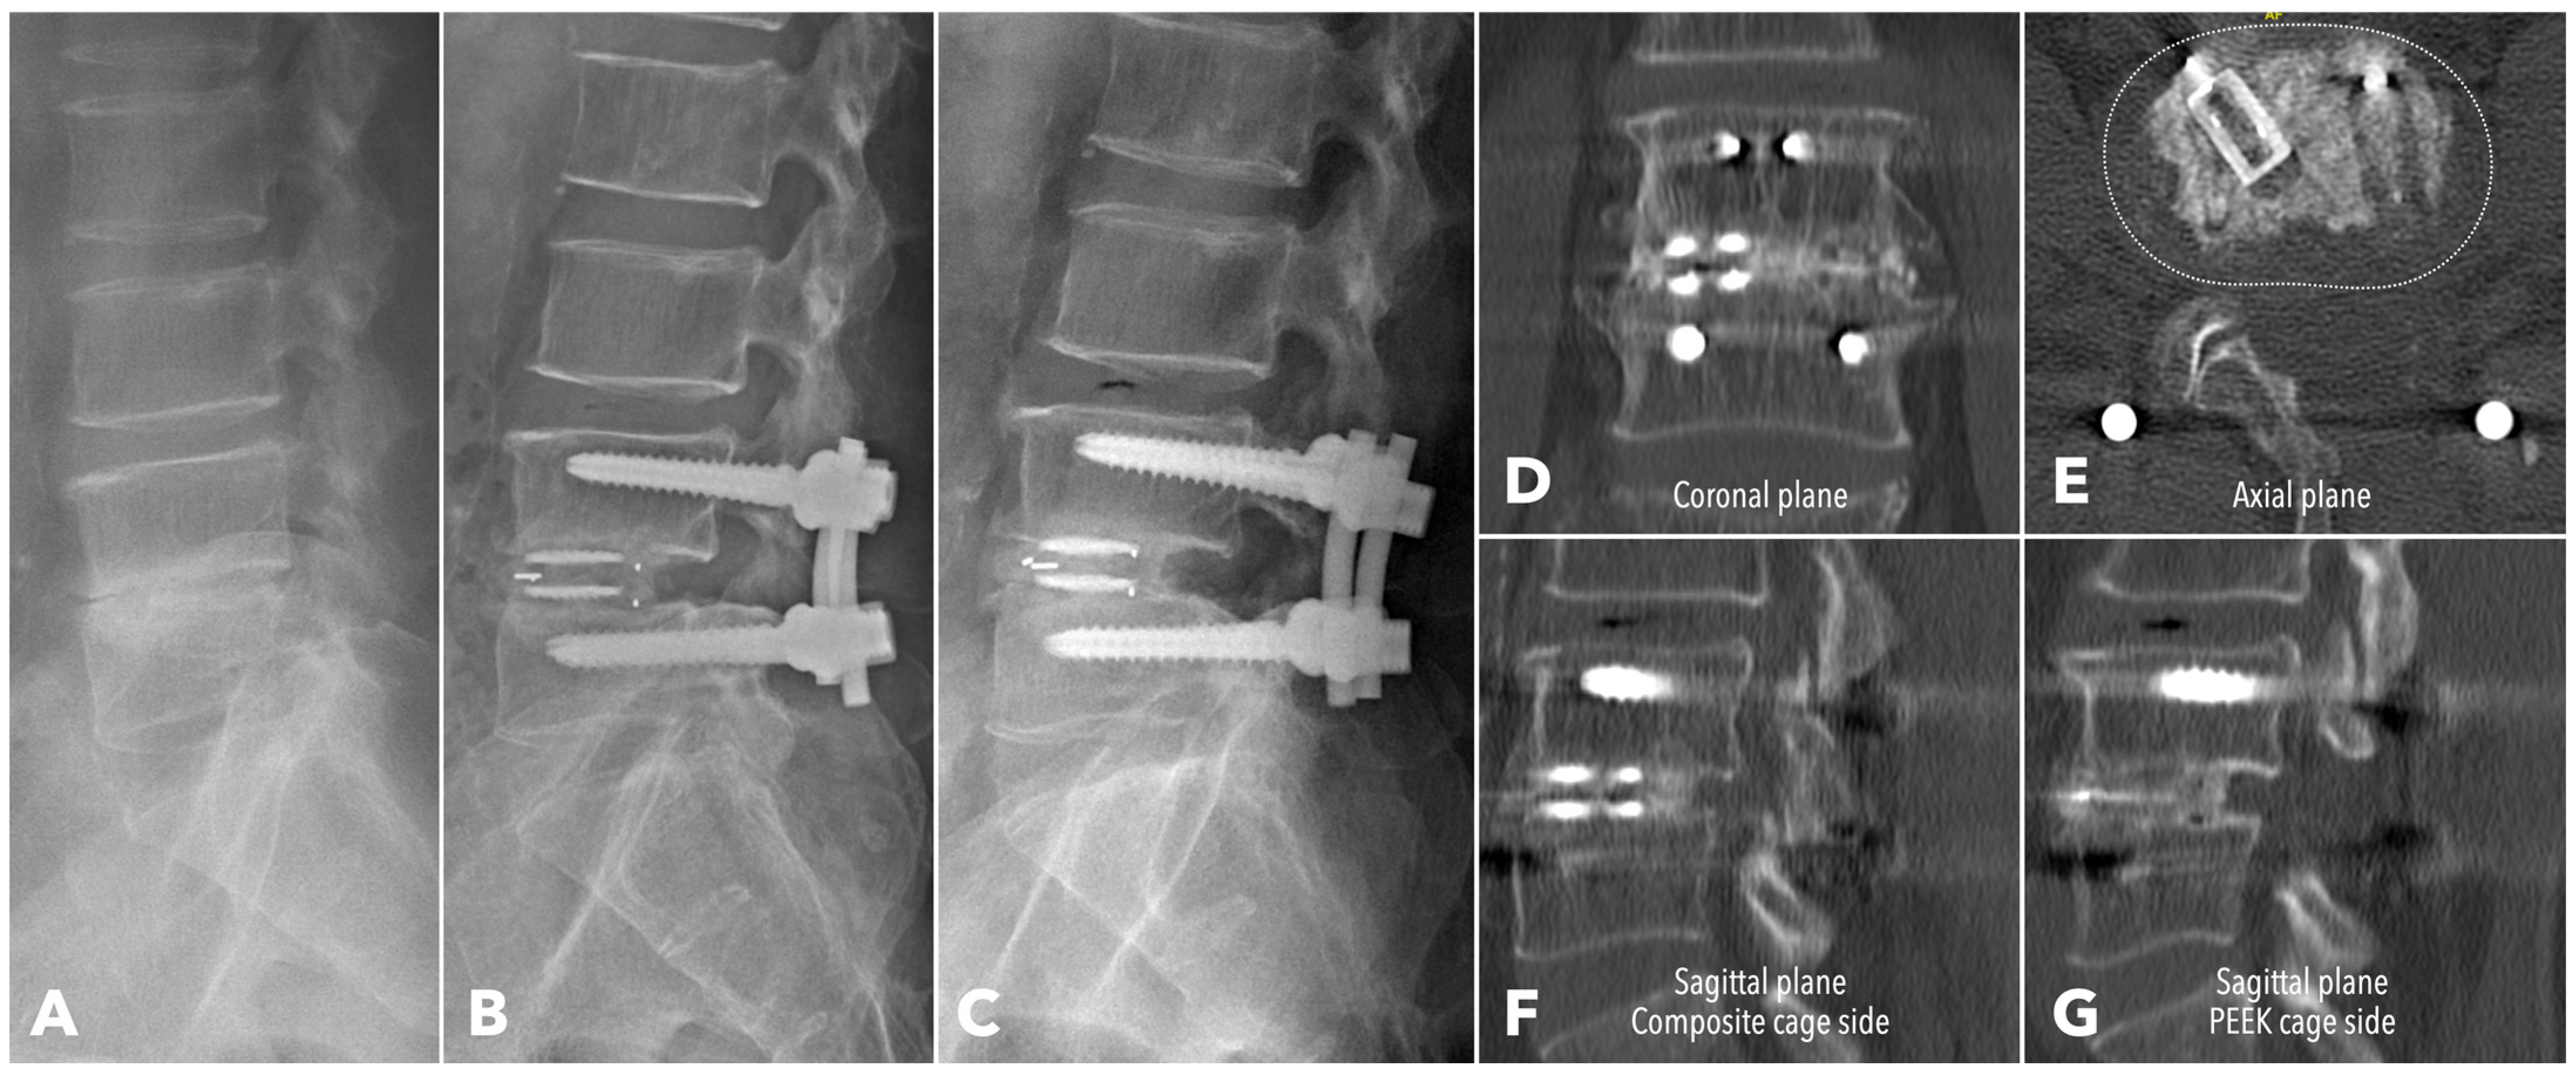

Among the segments evaluated by CT at one year (56.7% in MISTLIF vs. 67.4% in BETLIF, q = 0.216), the BETLIF group showed significantly higher rates of bridging bone in the sagittal (96.6% vs. 88.2%, p = 0.027) and coronal planes (93.3% vs. 82.4%, p = 0.025). The overall fusion success rate (Bridwell Grade I or II) was significantly higher in the BETLIF group (93.3% vs. 82.4%, p = 0.025). However, these statistical significances were eliminated after applying the Benjamini–Hochberg correction to control the FDR. Furthermore, a substantially higher proportion of BETLIF cases were classified as Bridwell Grade I (73.3% vs. 19.6%, q < 0.001), indicating superior fusion quality (Figure 6 and Figure 7).

Figure 7. A 62-year-old male patient underwent BETLIF at L4-5 due to painful disc degeneration with restoration of the disc height after the surgery (A,B). The postoperative 6-month X-ray showed consolidation of the bone graft (C). The 1-year CT scan revealed Bridwell grade I solid fusion with remodeling of the bone graft at both coronal plane (D) and sagittal plane (F,G) reconstructions. The axial plane reconstruction (E) demonstrated the cage footprint and the fusion bed. The white dashed line indicates the margin of the vertebral body.